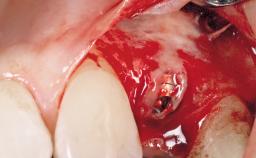

Immediate Flapless Placement of an Implant in a Maxillary Left Central Incisor Site

A 29-year-old female patient presented for treatment to replace the upper left central incisor tooth with an implant- supported restoration. The tooth had been intermittently symptomatic for the previous 12 months. The tooth had originally suffered trauma about 15 years previously. Several endodontic treatments had been performed, including an apicectomy procedure to retain the tooth. The patient was healthy and a non-smoker. She had reasonable expectations in regard to esthetic outcomes and the risk of marginal tissue recession following treatment. At medium smile, the gingival margins of the upper teeth were visible, with a display of 3 to 4 mm of the gingival margins. Gingival recession of tooth 21 and a discrepancy in the gingival levels between teeth 11 and 21 was observable during normal speech and smile.

Placement Protocol Immediate implant placement

Socket Integrity Damage to one or more bone walls

Bone Volume Damage to one or more socket walls